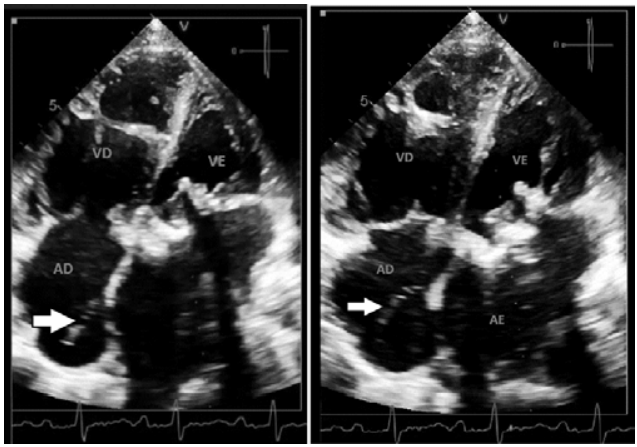

Paciente de 55 anos de idade, sexo feminino, em avaliação da prótese biológica em posição mitral com provável estenose, apresenta uma estrutura móvel em átrio direito (de acordo com a seta).

Com base nessa situação hipotética, assinale a alternativa correta que correlaciona a estrutura apontada pela seta e outro achado que pode estar associado à sua presença.

Imagem: arquivo pessoal.